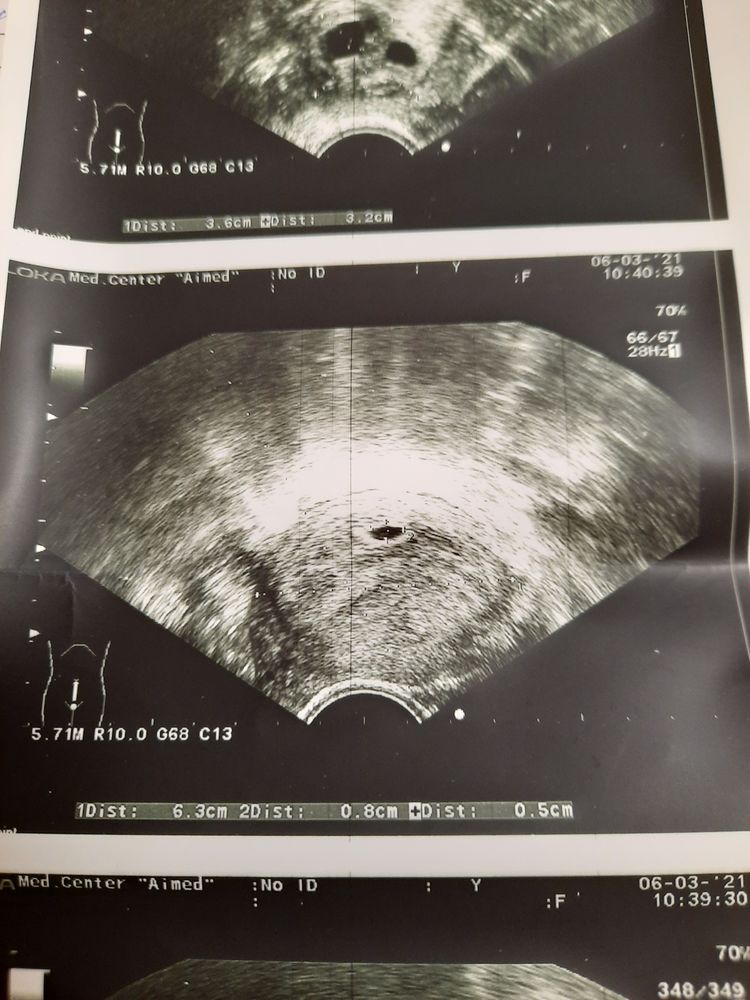

24 дпп размер пя?

Можно ли по фото узи определить размер пя?

24 дпп какой размер пя? 31 дпп узи